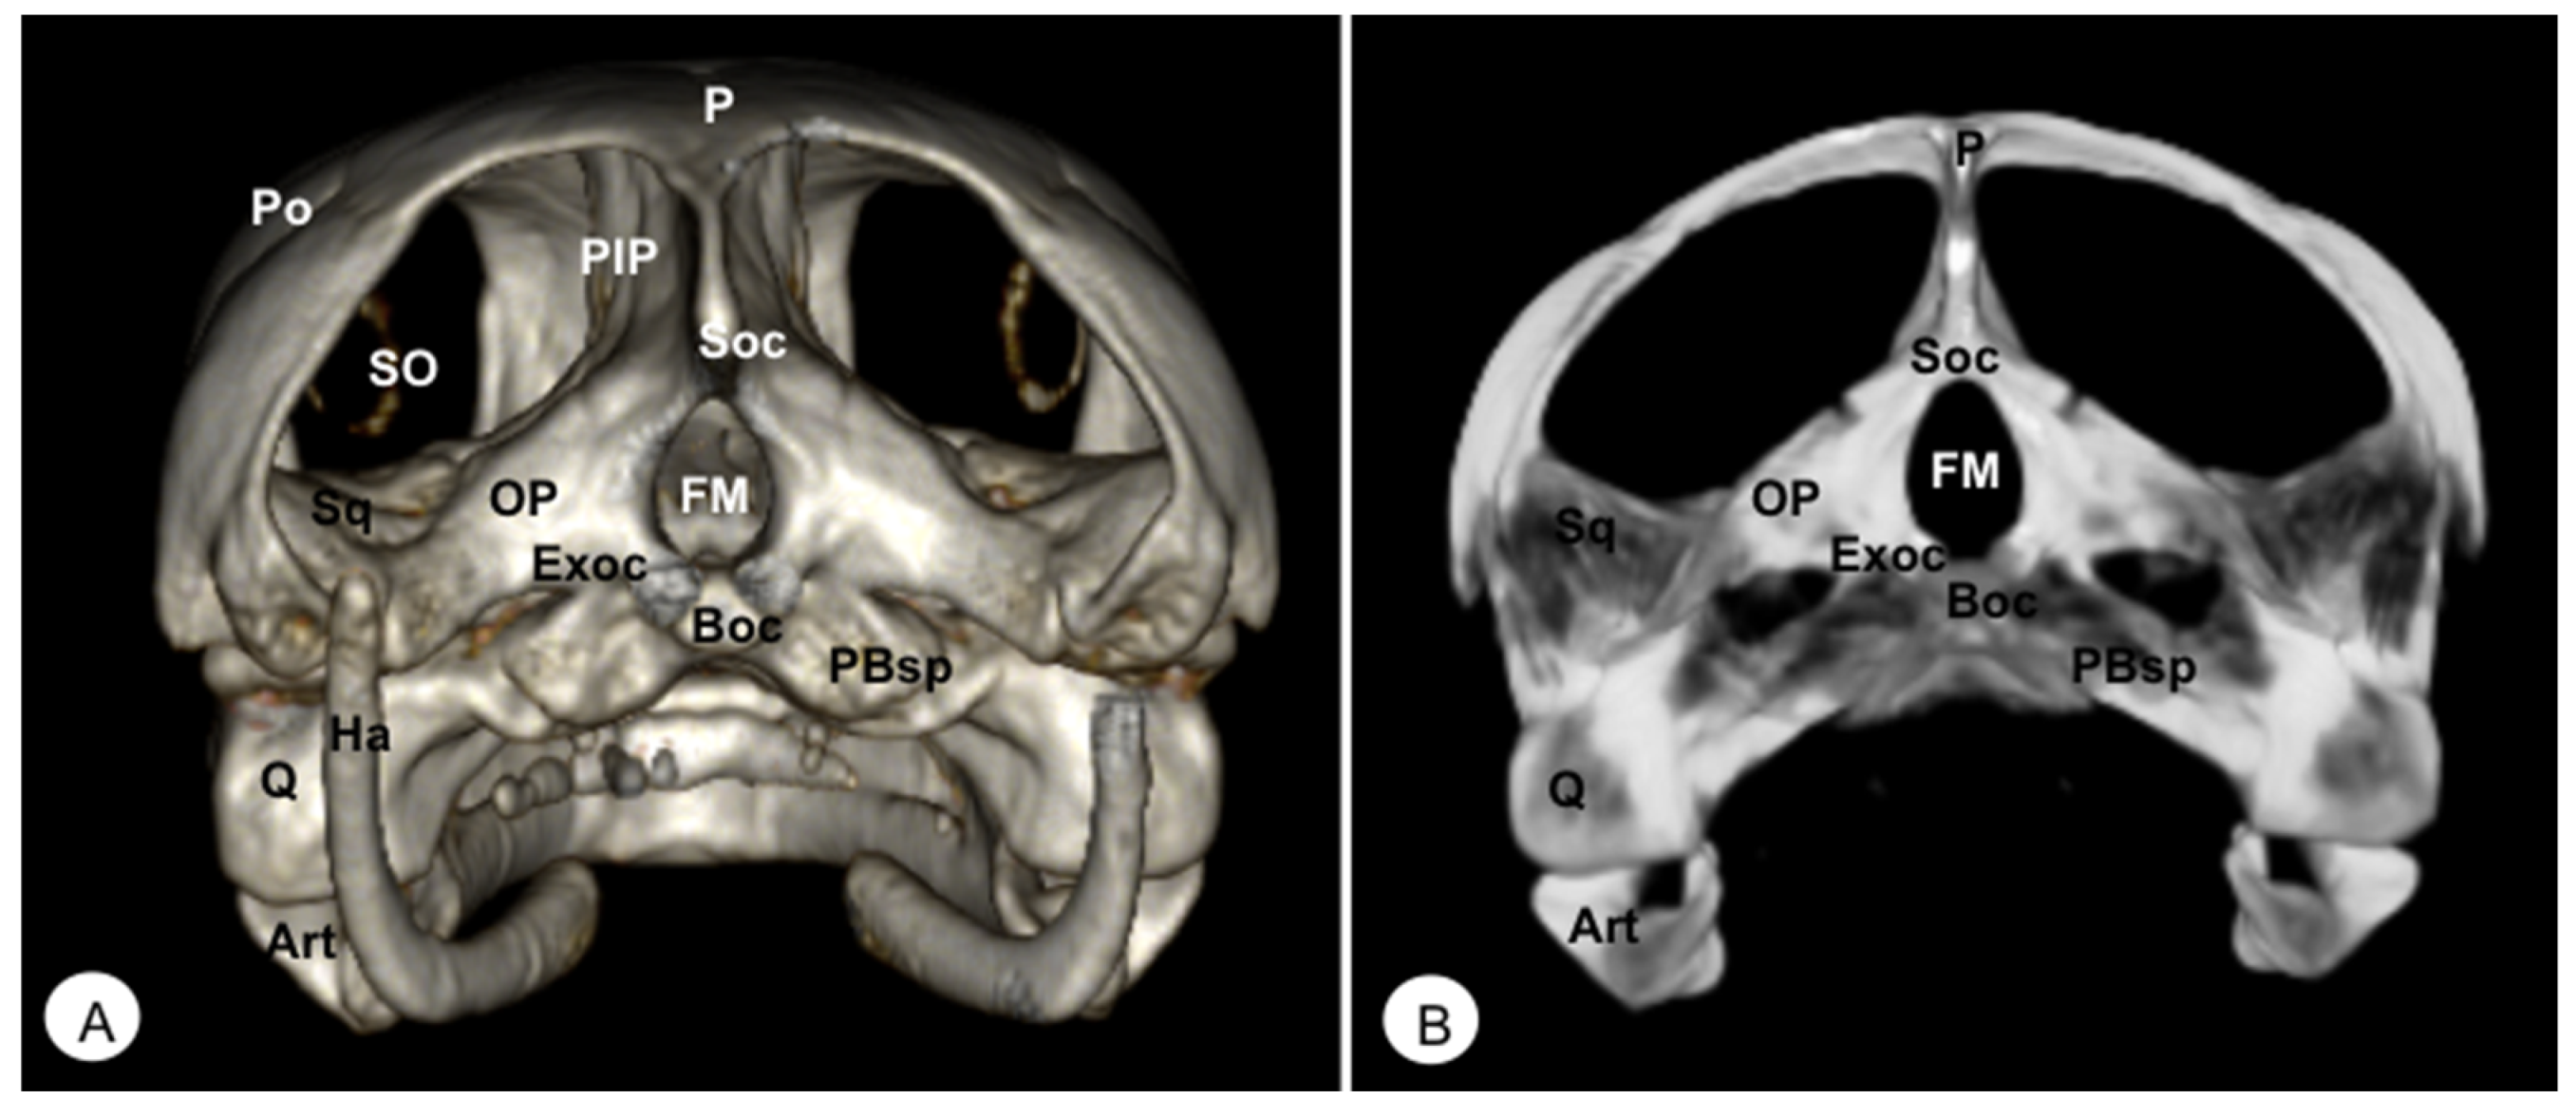

Figure 6. Head of Caretta caretta. (A) Caudal VR image. (B) Caudal MIP image. P: Parietal bone. PIP: Procesus inferior parietalis. Po: Postorbital. Sq: Squamosal bone. Soc: Supraoccipital bone. Exoc: Exoccipital bone. Boc: Basioccipital bone. OP: Opisthotic bone. FM: Foramen magnum. PBsp: Parabasisphenoid bone. SO: Scleral ossifications. Q: Quadrate. Art: Articular. Ha: Hyoid apparatus.

The supraoccipital bone is an unpaired midline element located in the posterodorsal portion of the skull (Figure 3, Figure 4, Figure 5, Figure 6, Figure 10 and Figure 11). Both turtles and iguanas have a similar configuration. This bone has a broad contact with the posteromedial margins of the parietals (Figure 3B, Figure 5A, Figure 10 and Figure 11). Posteroventrally, it contacts the opisthotic and otoocipital, forming part of the medial part of the occipital condyle, near the foramen magnum (Figure 6 and Figure 11). These features were observed by VR and MIP reconstructions in the caudal view of both species.

3.2.4. EXOCCIPITAL (Os Exoccipitale)

This bone is a paired bone that lies lateral to the foramen magnum and comprises part of the occipital condyle. Dorsally, it is in contact with the supraoccipital, anterodorsolaterally with the opisthotic bone, and ventromedially with the basioccipital bone (Figure 4A, Figure 5A and Figure 6). The exoccipital forms the posterior border of the metotic fissure. The ossification extends ventrally to the dorsolateral aspect of the occipital condyles, where it joins the basioccipital bone (Figure 4A).

The basioccipital bone in the turtle is a rectangular-shaped bone located in the posterior half of the planum basale, contacting the basisphenoid (rostrally) and exoccipital (caudally) bones, forming part of the floor of the cavum cranii (Figure 3B, Figure 4 and Figure 6). In the iguana, it roughly reaches the parabasisphenoid and caudally the occipital bone (Figure 11), forming part of the occipital condyle.

3.2.3. SUPRAOCCIPITAL (Os Supraoccipitale)